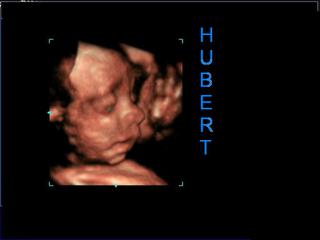

tak včera sme boli na 4D. Nechcela som ísť, ale naozaj by som strááášne ľutovala. Úžasné to bolo. Proste od začiatku po koniec sme boli v nemom úžase, slzy mi tiekli celý čas ...Bola som nadšená ako nám lekár všetko pozrel, ako tečie krv, koľko žíl má pup.šnúra, ako bije srdiečko, ako má vnútorné orgány v poriadku ... no samozrejme malý sa nechcel ukázať stále tam mal ručičku, alebo nožičku - lekár aj šťuchal ale stále sa zakrýval. No ale nakoniec máme nádherné dvd ako spinká na jednej ruke a zívlo sa mu, vyplazil jazýček ... usmial sa a spinkal ďalej ... Lekár bol taký ochotný že mi pozrel aj krčok, aj či je všetko ako má byť. Vraj krčok má 3,64 čo je skvelé a všetko je zatvorená ako má byť ... Veľmi bol milý, boli sme tam vyše hodiny a štvrť, ale manžel mal toľko otázok ... podľa jeho výpočtu sme o tt napred, podľa sona o 2 dni, takže si myslím že sme akurát . Prikladám fotku malého nezbedníka - ktorý nám to šťuchanie vrátil a od 2,02 hod. som nespala - ale keďže ja tie jeho kopančeky milujem, rada sa nevyspím ešte 100 dní, len ak bude zdravučký ...